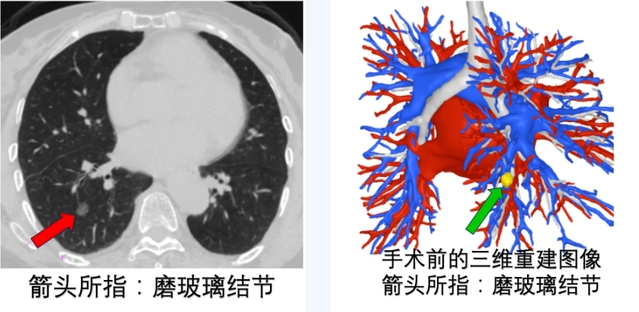

一月前,患者体检发现肺部磨玻璃结节,结节大小达11mm。家属慕名到苏州九院请施舜缤主任就诊。施舜缤主任将患者收住入院,并进行了充分的鉴别诊断和术前准备。

考虑到患者年龄较大、肺功能较差,肺结节的磨玻璃成分相对较多,手术的话,不必行肺叶切除。但是,患者的肺结节位置比较刁钻,位于下肺叶的基底段内,横跨了2个基底段,在2个相邻的亚段内。

早期肺癌,尤其是以磨玻璃为主的肺结节,体积常常比较小。临床上,常常只需要切除肺结节所在的相应肺段或者亚段即可。如果肺结节跨越亚段,没有局限在同一个亚段内,这种情况常常需要做联合亚段的切除术。肺亚段切除术仍然存在一些挑战。因为从解剖上讲,肺叶的解剖变异比较少,肺段的解剖变异就比较多了,亚段的解剖变异就更多了。因此,肺亚段切除术的手术技术要求较高,需要经验丰富的外科医生进行操作。手术前,常常需要作好三维立体重建,明确手术的范围、路径等。在选择肺亚段切除术作为治疗方案时,医生需要综合考虑患者的具体情况,权衡手术的风险和收益。